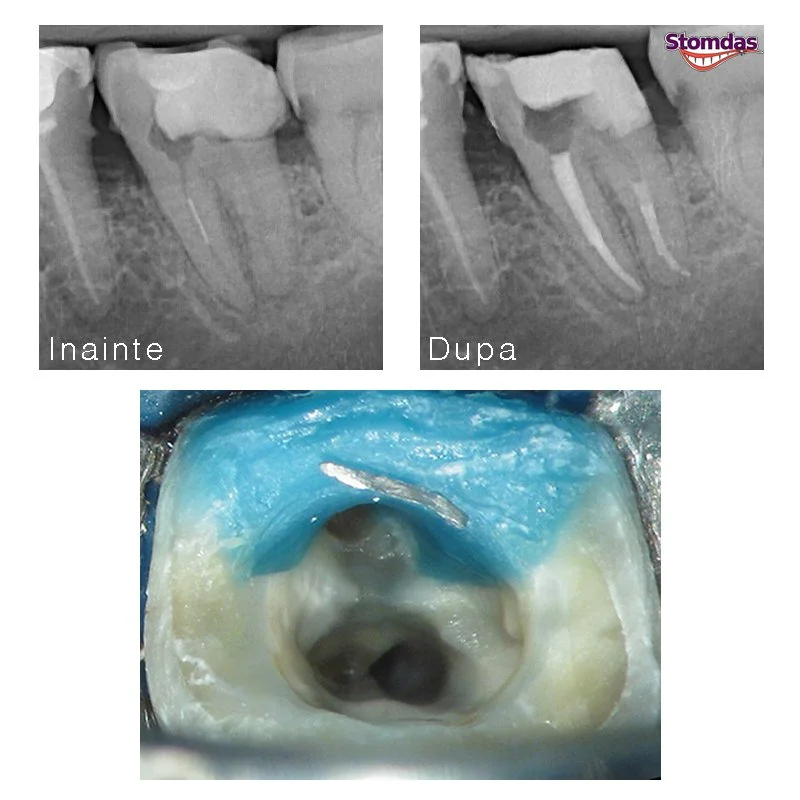

Tratamentele stomatologice sunt o investitie pe termen lung daca aveti grija de dintii dumneavoastra. Noi avem grija sa facem ce trebuie si cum trebuie si cand pacientii ne respecta recomandarile totul merge bine mult timp. In radiografiile alaturate puteti vedea cazul unui pacient cu o infectie mare la nivel osos, care s-a vindecat dupa retratarea dintilor corespunzator sub control microscopic, fara revenirea simptomatologiei nici macar la 8 ani dupa tratament.

Acele rupte in canal prezinta o problema reala in stomatologie, deoarece nu permite efectuarea corecta a tratamentului, ceea ce va duce la aparitia sau agravarea unei infectii. In acelasi timp, atat depasirea cat si extragerea lor, care este necesara pentru succesul tratamentului, are o rata crescuta de risc si accidente daca sunt efectuate fara magnificatie. Tratamentul la microscop reprezinta varianta cea mai sigura si eficienta de rezolvare a acestei probleme.